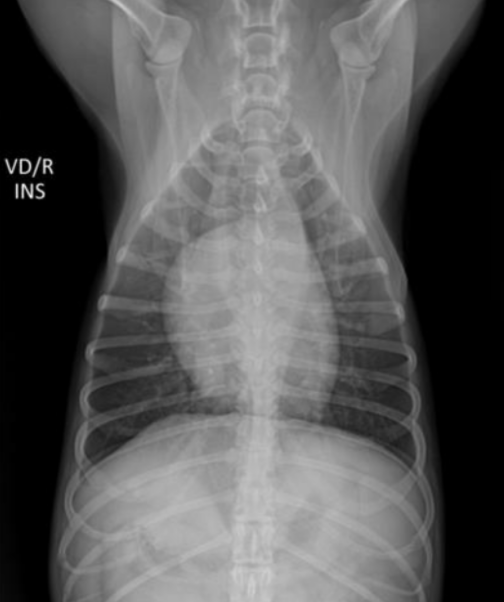

| Inspiration | Expiration |

|---|---|

![]() | ![]() |

| - ํ ๋ถ๋ถ์ด ๋ opaque (๋ฟ์๊ฒ ๋ณด์) | |

| - ํก๊ฒฉ๋ง์ด ๋ ์๋ก ์ฌ๋ผ์ ์ฌ์ฅ๊ณผ ๋ถ์ด ์์. |